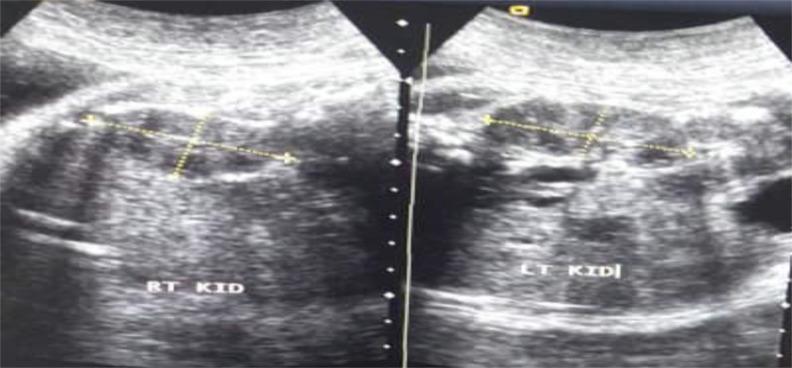

Foetal kidney length (FKL) measurements and comparisons to normal charts can be used to assess the development of the foetal kidneys throughout the entire course of pregnancy. This study was designed to assess FKL between 20 - 40 weeks' gestation, establish reference ranges for FKL and determine the relationship between FKL and gestational age (GA) in normal pregnancy.

This descriptive, cross-sectional study was conducted between March-August 2022, at the Obstetric Units and Radiology Departments of the two tertiary health facilities, one secondary facility and one radio-diagnostic facility in Bayelsa State, Southern Nigeria. Transabdominal ultrasound scan was used to evaluate the foetal kidneys. The relationship between foetal kidney dimensions and GA was explored using Pearson's correlation analysis. Linear regression analysis was done to define the relationship between GA and mean kidney length (MKL). A nomogram predicting GA from MKL was constructed. Level of significance was set at p<0.05.

There was a very strong significant correlation between foetal renal dimensions and GA. The correlation coefficient between GA and mean FKL, width and anteroposterior diameter were 0.89 (p=0.001), 0.87 (p=0.001) and 0.82 (p=0.001), respectively. A unit change in mean FKL corresponded to a 79% change in GA (ɼ2), showing a very strong association between mean FKL and GA. The regression equation: GA = 9.87 + 5.91 x MKL, was derived for estimation of GA for a given MKL.

Our study revealed a significant relationship between FKL and GA. The FKL can therefore be reliably used to estimate GA.